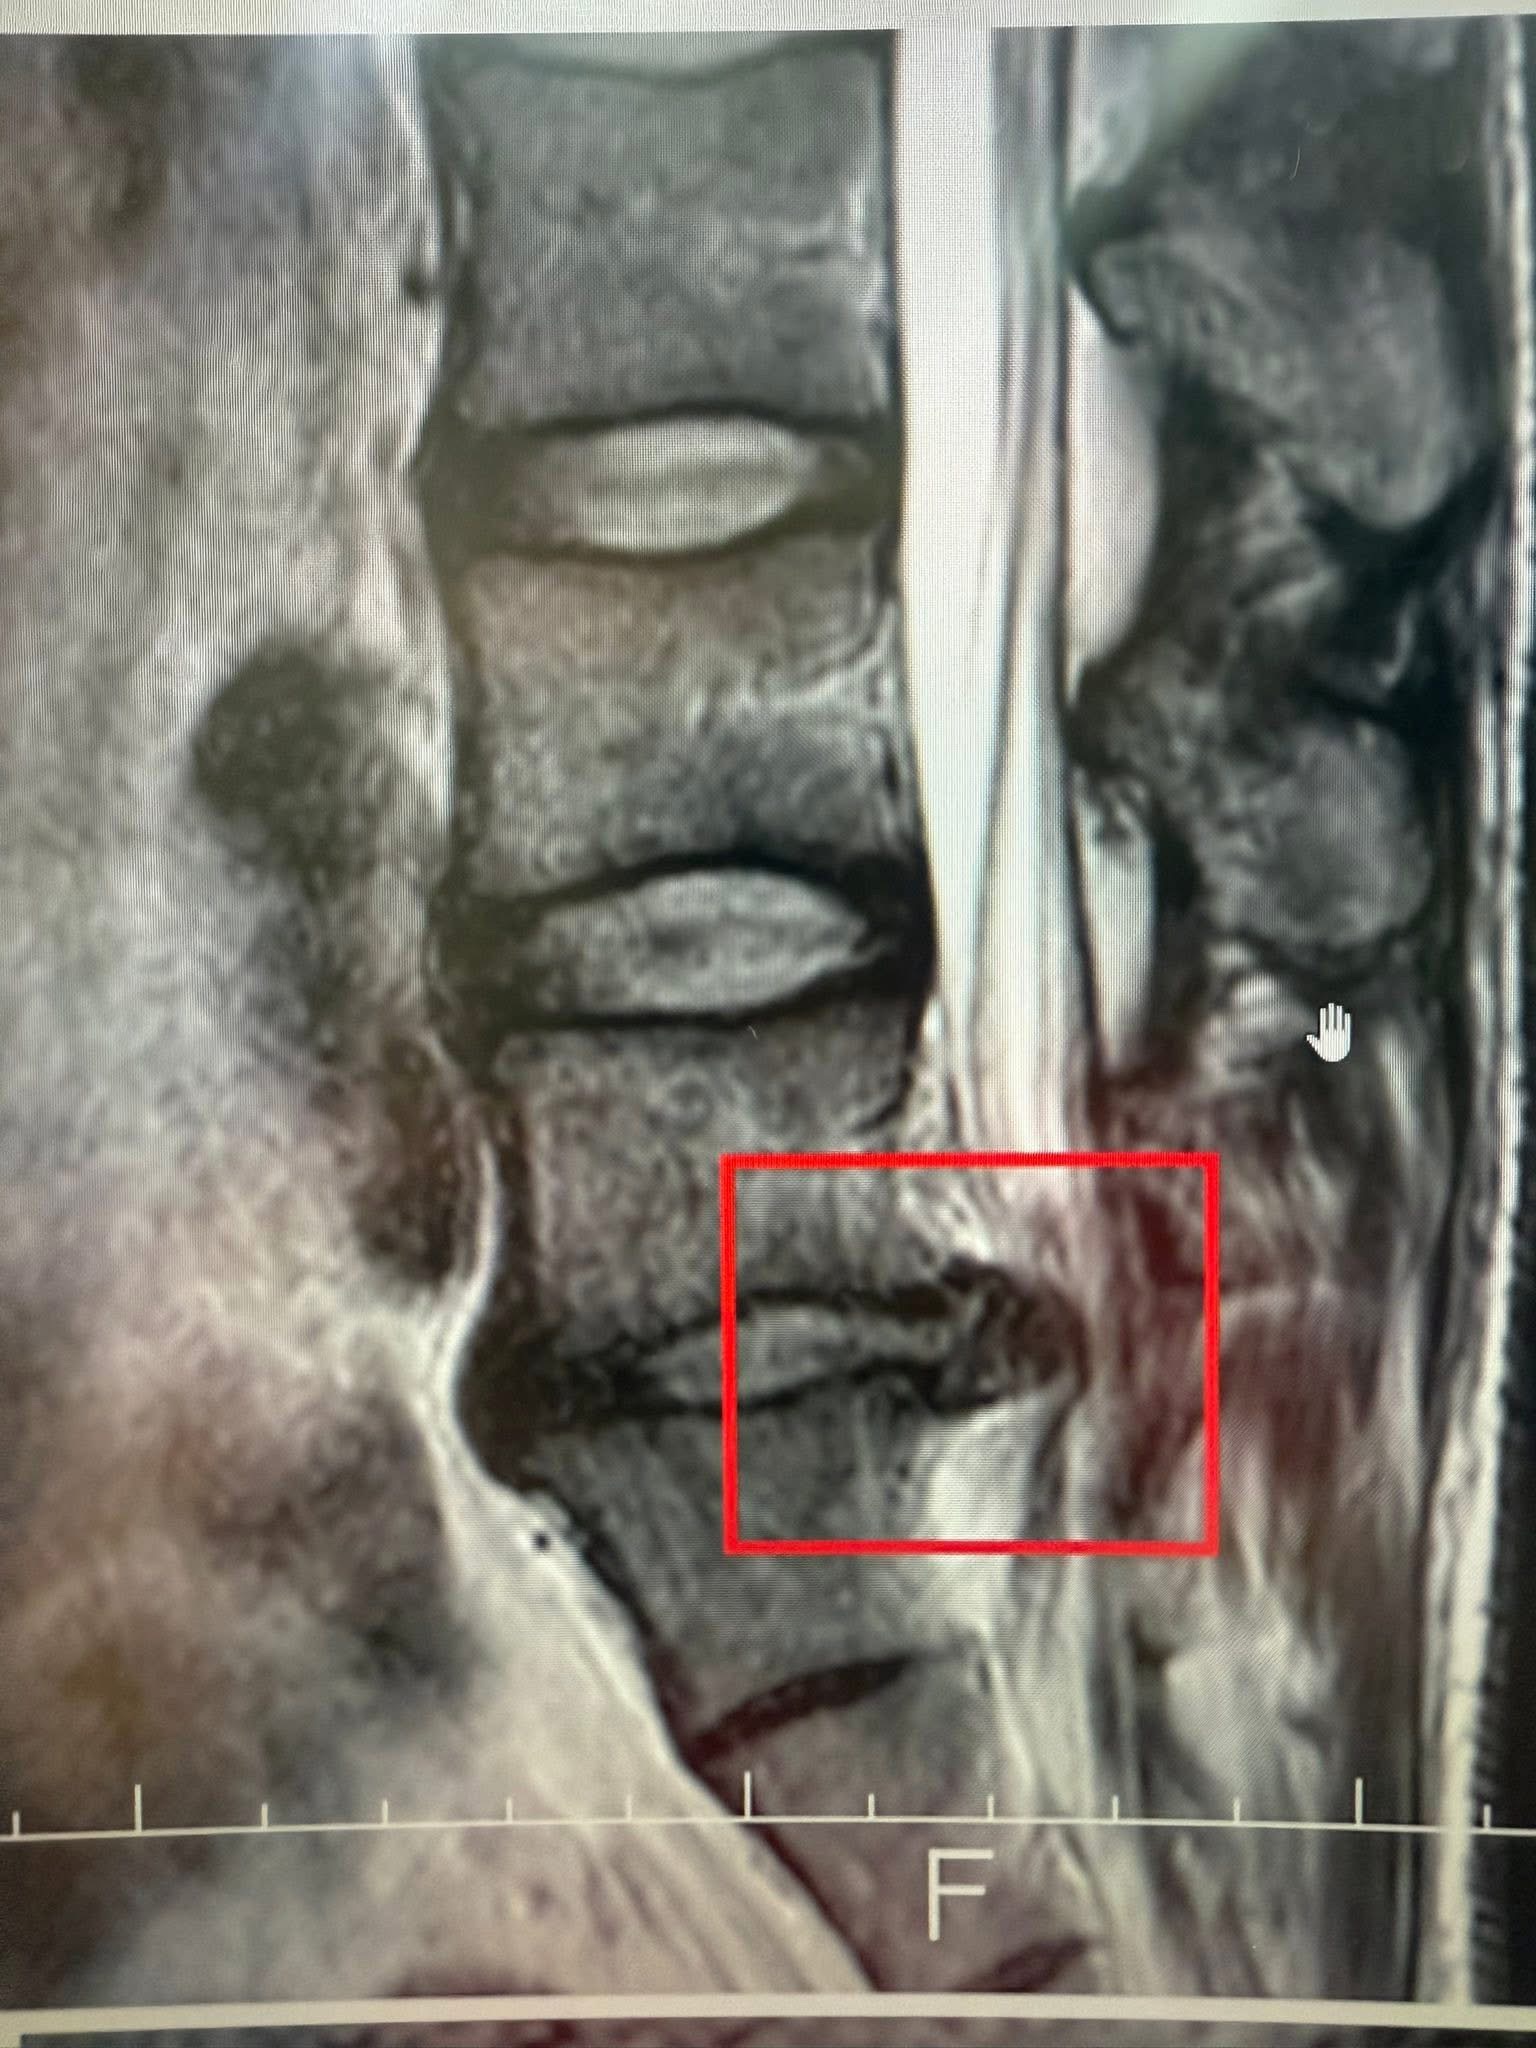

經詳細詢問病史,他患有L5/S1巨大椎間盤突出,導致左側坐骨神經嚴重壓迫,出現典型的「痠、麻、脹、痛、跛行」。過去兩個月,他已在在地復健科接受常規治療——熱敷、電療、牽引——但效果不彰,甚至一度惡化。

✅疼痛持續超過12周或病人出現進行性神經功能障礙時建議拍攝核磁共振。